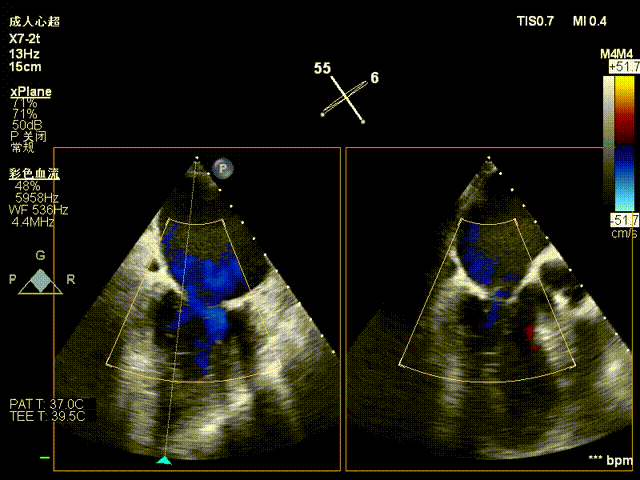

术前影像

二尖瓣后瓣腱索断裂并脱垂及关闭不全(重度)